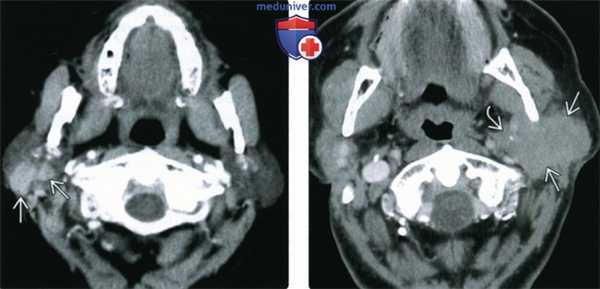

(Слева) КТ с КУ, аксиальная проекция. Множественные образования в правой околоушной железе, которые имеют четкие контуры и равномерно накапливают контрастное вещество. Какие-либо другие очаги обнаружены не были, поэтому пациенту был выставлен диагноз первичной неходжкинской лимфомы околоушных лимфоузлов.

(Справа) КТ с КУ, аксиальная проекция. Первичная MALT-лимфома околоушной железы. Инфильтративное образование поражает поверхностную и глубокую доли железы, симулируя агрессивную злокачественную опухоль. Для лимфоцитарной лифомы более характерны четкие края.

(Слева) На аксиальной КТ с КУ справа визуализируются множественные односторонние интрапаротидные опухоли с четкими краями, равномерно накапливающие контраст. Признаки заболевания вне околоушной железы отсутствуют, вследствие чего было сделано заключение о первичной нодальной НХЛ околоушной железы.

(Справа) На аксиальной КТ с КУ определяется первичная MALT-лимфома околоушной железы. Инфильтративное новообразование поражает поверхностную и глубокую доли, имитируя агрессивную первичную опухоль слюнной железы. Лимфоцитарные лимфомы могут иметь более четкие границы.